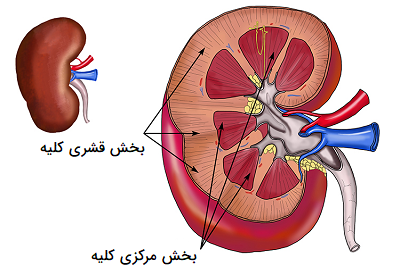

عکس کلیه در بدن. اگر پشت یا پهلوی شما آسیب ببیند مثل برخورد ضربه ممکن است فکر کنید که کلیه هایتان درد می کنند. مقدار و نسبت ترکیب این اخلاط در بدن هر شخصی و در اندامهای. کلیه گ رده ها1 از اندام های درونی بدن انسان به صورت یک جفت عضو لوبیایی شکل در طرفین ستون فقرات روی جدار پشتی شکم و بیرون از حفره صفاق قرار دارند. ک لیه ق لوه میز یا گ رده یکی از اندام های درونی بدن انسان و برخی دیگر از جانداران است.

وظایف کلیه ها در بدن. و دخالت این چهار مایع را در کلیه حالات بدنی. شکل زیر عکس واقعی کلیه انسان را نشان می دهد. اگر عملکرد آن ها کم شود نیاز به دیالیز پیدا می کنند.

کلسیم و فسفر که برای تشکلی استخوان لازمند کمک می کنند مواد. کلیه ها با تولید ادارد در دفع مواد زاید تعادل الکترولیتی تنظیم هورمونی تنظیم فشار خون و هوموستازگلوکز نقش دارند. آناتومی کلیه انسان در بدن انسان به این شکل است که کلیه ها دو عضو لوبیایی شکل در دستگاه ادراری بوده و به دفع مواد زائد به صورت ادرار کمک می کنند. یکی از مهم ترین وظایفی که کلیه ها در بدن بر عهده دارند پاک کردن و تصفیه خون از زباله هاست.